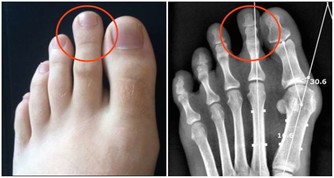

輕微缺乏維生素B2人體不會有任何感覺,但到一定程度時就會出現明顯的症狀,首先,在人體最薄弱的地方,通常是消化道的首尾兩端,即口腔或肛門的局部,出現充血、腫脹,隨後皮膚或粘膜出現潰瘍,然後開始出血,這即是口腔潰瘍和痔瘡。如果長期缺乏維生素B2,那麼人體其它部位也會出現同樣的症狀。

3、痔瘡也是因為缺乏維生素B2引起的。